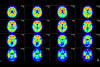

MRI and AI could significantly reduce pediatric brain tumor diagnosis time Children with the most common malignant form of brain cancer could see diagnostic wait times reduced thanks to new research that trialed a new, quicker and less invasive way of determining which type of tumor they have.

The 10-minute test for childhood tumours Children with cancer could have an accurate brain tumour diagnosis in 10 minutes, thanks to new research. There are four types of medulloblastoma, the most common form of brain cancer, and treatment differs between patients.